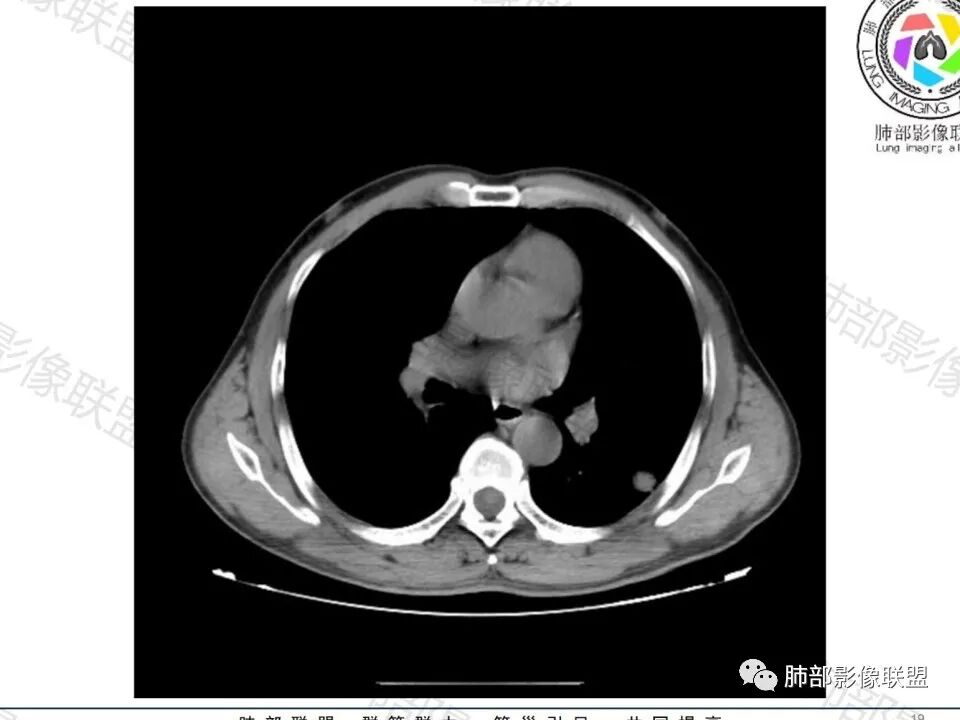

这枚结节的纵隔窗在没有调节窗位的情况下,已经很密实了,说明这个结节里面是软组织的成分,这与普通炎性结节(隐球菌等)的密度还是有区别的,很多年前就有人提出,纵隔窗显示越大,恶性可能越大;

结节周围有磨玻璃影,边界似清不清的,但是总体不如炎性晕征那么模糊;

增强的程度很难讲,但是不均匀强化是可以确定的;

有收缩力,但是很轻,按照常理,实性结节因为有占位效应,不太会有收缩力,但是叶间胸膜有凹陷。所以讲,这个结节还是开了放心。